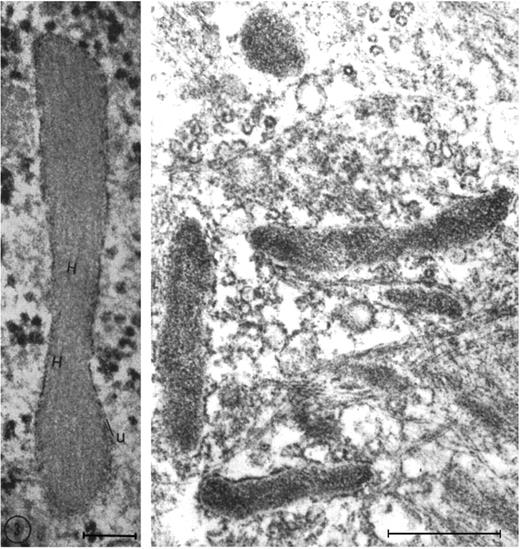

One of the key developments was the isolation and in vitro culture of endothelial cells in the early 1970s by Jaffe et al9 and Gimbrone et al10 who taught many, including one of us (D.D.W.), this art. The presence of a unique organelle discovered by Weibel and Palade in 196411 turned out to be an important marker to identify bona fide endothelial cells (Figure 2 left). This organelle, now called the Weibel-Palade body (WPB), was found in 1982 by Wagner et al12 to represent the storage granule for von Willebrand factor (Figure 2 right), a molecule mediating platelet adhesion. A few years later, a receptor for leukocytes (P-selectin) was found in its membrane.13,14 Thus, the secretion of these organelles provides a very rapid way for the activated endothelium to become adhesive for platelets and leukocytes. Treatment of endothelial cultures with cytokines by Bevilacqua et al showed another way to augment endothelial adhesiveness for leukocytes15 (Figure 3).

Weibel-Palade bodies are endothelial-specific organelles that store von Willebrand factor. (Left) Oblique section of a Weibel-Palade body from pulmonary artery endothelium of a rat, showing parallel arrangement of internal tubules (H). Reproduced with permission from Weibel and Palade.11 (Right) Electron micrograph (Wagner et al12 ) of human umbilical vein endothelial cells stained for von Willebrand factor with peroxidase showing a cluster of positively stained Weibel-Palade bodies. Left bar is 0.1 μM, and right bar is 0.5 μM. Reproduced from The Journal of Cell Biology.11,12 Copyright 1964 and 1982 The Rockefeller University Press.